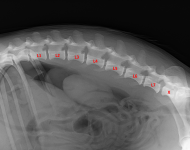

(5) 7 měsíců lat

(5) 7 měsíců lat

(5) typ 3 páteř VD

(5) typ 3 páteř VD